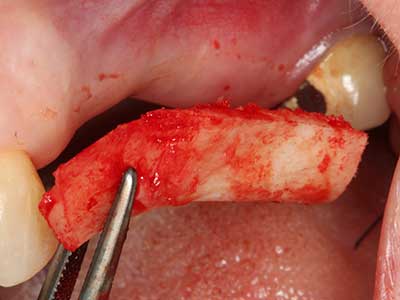

En la extracción de bloques óseos la piezocirugía también presenta ventajas adicionales: Además de la alta precisión en la osteotomía que ya se ha descrito antes, se ha comprobado que el uso de los delgados insertos de sierra resulta especialmente cuidadosas con el hueso. Frente a esto, sobre todo cuando se usan las fresas de Lindemann, cabe esperar pérdidas en la extracción significativamente más altas debido al mayor grosor de la parte frontal del cabezal (Lakshmiganthan, Gokulanathan et al. 2012). La separación basal que se necesita en particular en los injertos de bloque extraídos de forma retromolar se ve facilitada mediante sierras perpendiculares especialmente previstas a tal fin, lo que permite considerar que la cirugía piezoeléctrica es un procedimiento preciso y seguro para la obtención de bloques de hueso en el área retromolar (Happe 2007) (fig. 1-12).

Fig. 3: La separación basal del bloque se ve facilitada con piezas dotadas de una angulación especial.

Fig. 4: Con la rasqueta ósea se obtienen virutas adicionales de hueso autógeno.